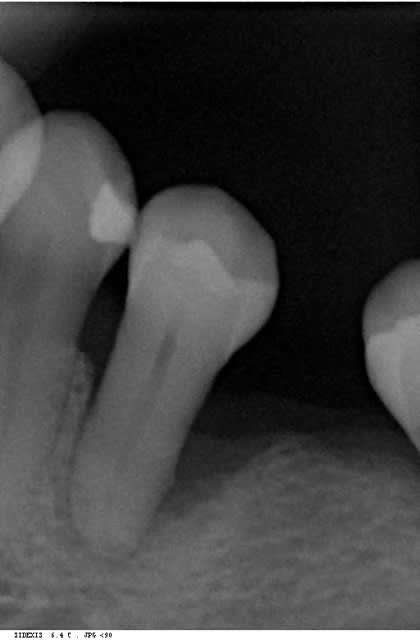

> voila comme promis les 2 cas cliniques.

>

> patiente 1 : paro aggressive, importantes lésions

> angulaires traitées par emdogain sauf mesial 33 où

> j'ai préféré faire une GTR avec comblement

> BioOss.

Superbes résultats !

1 La conservation de la 28 n'est elle pas un facteur défavorable ?

2 la 26 a t'elle été extraite en première intention ou après un échec de la régénération ?

3 avais tu dans ce cas une espèce bactérienne spécifique ?